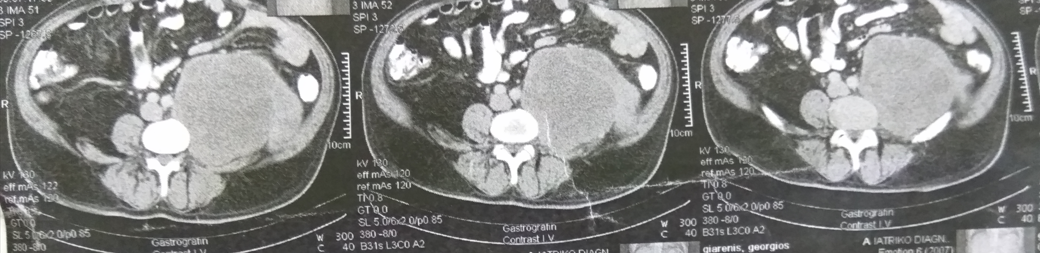

Ένας 68χρονος ασθενής , εισήχθη σε επαρχιακό νοσοκομείο , παραπονούμενος για οξύ κοιλιακό άλγος , δυσχέρεια αναπνοής και πτώση της αρτηριακής πίεσης. Μετά την αρχική αναζωογόνηση , έγινε αξονική τομογραφία κοιλίας , η οποία ανέδειξε την παρουσία , ευμεγέθους , πολυλοβωτής , χαμηλής πυκνότητας , εξεργασίας μαλακών ιστών , στην περιοχή του αριστερού λαγονίου βόθρου , ενδεικτικών διαστάσεων 10 Χ 6.8 εκ . που ανέρχονταν προς τα επάνω , μέχρι τον κάτω πόλο του αριστερού νεφρού , ενώ κατέρχονταν όπισθεν των έξω λαγονίων αγγείων , μέχρι το ύψος των κοκκυγικών σπονδύλων ( ενδεικτική κεφαλουραία διάμετρος 16.4 εκ . ) . Τα υπόλοιπα όργανα της κοιλίας ήταν φυσιολογικά , όπως φυσιολογική ήταν και η εκτελεσθείσα σε 2ο χρόνο αξονική τομογραφία θώρακος , χωρίς την ανάδειξη μεταστατικών εστιών στο ήπαρ ή στους πνεύμονες . Μετά την σταθεροποίηση του , ο ασθενής ανέφερε ότι βίωνε ένα αμβλύ άλγος στην αριστερή οσφύ , τους τελευταίους 2 μήνες , το οποίο απέδιδε στην δυσκοιλιότητα . Από το ατομικό και οικογενειακό ιατρικό ιστορικό , δεν υπήρξε κάτι το άξιο λόγου . Κατά την κλινική εξέταση , διαπιστώθηκε εκσεσημασμένη διάταση κοιλίας , με σύσπαση αριστερά χωρίς περιτοναισμό και βύθιους εντερικούς ήχους . Υπήρξε αδυναμία ψηλάφησης μαζών . Η Hb ήταν 8 gr , οπότε και μεταγγίστηκε με δύο μονάδες ερυθρών κυττάρων . Ο χρόνος προθρομβίνης ήταν φυσιολογικός , όπως ήταν οι ηπατικές δοκιμασίες και οι λοιπές βιοχημικές εξετάσεις . Τα επίπεδα των κατεχολαμινών , της κορτιζόλης και της αλδοστερόνης ήταν εντός των φυσιολογικών ορίων . Την επόμενη ημέρα , με απαίτηση της οικογένειας του , ο ασθενής διακομίστηκε στην κλινική μας για περεταίρω αντιμετώπιση . Εικόνα 1 . CT Scan Κοιλίας . Τεράστια οπισθοπεριτοναική μάζα αριστερά . ( Αρχείο κος Β . Πενόπουλος ) . Αφού λάβαμε υπ’ όψιν μας , το αρνητικό για σοβαρές παθήσεις ιατρικό ιστορικό του ασθενούς , την παρουσία ενός εξαιρέσιμου οπισθοπεριτοναικού όγκου ο οποίος αιμορράγησε ( πτώση Α . Π . και Hb ) , την απουσία εγκλωβισμού / διήθησης κρίσιμων αγγείων από τον όγκο , την απουσία μεταστάσεων , την επαπειλούμενη απόφραξη του αριστερού ημικόλου και την ανάγκη μιας αξιόπιστης διάγνωσης , αποφασίσαμε να προχωρήσουμε στην εκτέλεση ερευνητικής λαπαροτομίας . Μετά την διάνοιξη της κοιλίας , διαπιστώσαμε την παρουσία αιμοπεριτοναίου , το οποίο προφανώς προεκλήθη από την ρήξη και την αιμορραγία του αγγειοβριθούς οπισθοπεριτοναικού όγκου . Μετά την αφαίρεση περίπου 1 λίτρου αίματος και θρόμβων , αποκαλύφθηκε μία εύθρυπτη , σκουρόχρωμη μάζα , διαστάσεων 10.5 Χ 7.2 εκ . , κάτωθεν του κάτω πόλου του αριστερού νεφρού , με ασαφή όρια , η οποία ήταν συμπεφυμένη στερεά με τον αριστερό ψοίτη μύ . Τα περιφερικά αγγειακά στελέχη ήταν ελαφρώς διατεταμένα ως εκ της πιέσεως της μάζας αλλά δεν παρατηρήθηκαν διακυμάνσεις της αρτηριακής πίεσης κατά την διάρκεια των χειρισμών του όγκου . Με προσεκτικούς χειρισμούς και παρά την αιμορραγική διάθεση του ασθενούς , κατέστη δυνατή η πλήρης αφαίρεση του όγκου χωρίς μείζονα αιμορραγία , συμπεριλαμβανομένων των τμημάτων όπισθεν των έξω λαγονίων αγγείων , en bloc μετά του κατιόντος κόλου και του σιγμοειδούς τα οποία θεωρήθηκαν διηθημένα από τον όγκο κατά συνέχεια ιστού - εγχείρηση κατά Hartmann . Εικόνα 2 . Αγγειοσάρκωμα . Διατομή παρασκευάσματος . ( Αρχείο κος Β . Πενόπουλος ) . Εικόνα 3 . Λεπτομέρεια εσωτερικού αγγειοσαρκώματος . ( Αρχείο κος Β . Πενόπουλος ) . Εικόνα 4 . Συρρικνωμένο κατιόν και σιγμοειδές κόλον . Κόκκινα βέλη . Διήθηση του παχέος εντέρου κατά συνέχεια ιστού . ( Αρχείο κος Β . Πενόπουλος ) . Εικόνα 5 . «Θυγατρικοί» όγκοι προσκολλημένοι προιερά . ( Αρχείο κος Β . Πενόπουλος ) . Η ιστοπαθολογική εξέταση , αποκάλυψε πως η οπισθοπεριτοναική μάζα , ήταν ένας κακοήθης όγκος , με ιστική νέκρωση στο εσωτερικό της νεοπλασίας . Τα καρκινικά κύτταρα ήταν επιθηλιοειδή κύτταρα με προφανή κυτταρική ατυπία και έντονη μιτωτική δραστηριότητα . Η ανοσοιστοχημική εξέταση , ανέδειξε θετική αντίδραση στην πανκυτοκερατίνη , βιμεντίνη και CD31 . Αντίθετα δεν υπήρξε αντίδραση σε διάφορους δείκτες , όπως το αντιγόνο της επιθηλιακής μεμβράνης , S100 , τον παράγοντα μεταγραφής SOX-10 , το μαύρο-45 του ανθρωπίνου μελανώματος , το melan-A , την ποδοπλανίνη , το CD117 , τον παράγοντα μεταγραφής-1 του θυρεοειδούς , την χρωμογρανίνη Α και την ακτίνη των λείων μυικών ινών . Τέλος , ο δείκτης του αντιγόνου Ki-67 , ήταν περίπου 50% . Εικόνα 6 . Επιθηλιοειδή καρκινικά κύτταρα , με προφανή κυτταρική ατυπία και μιτωτικές εικόνες . ( Αρχείο κος Β . Πενόπουλος ) . Εικόνα 7 . Ανοσοιστοχημική εξέταση-CD31 (+). ( Αρχείο κος Β . Πενόπουλος ) . Ο ασθενής είχε ομαλή μετεγχειρητική πορεία και εξήλθε του Νοσοκομείου μας 10 ημέρες αργότερα . Προ της εξόδου του , εκτιμήθηκε από ογκολόγο και προγραμματίστηκε να λάβει συμπληρωματική θεραπεία . Παρέμεινε ελεύθερος συμπτωμάτων , με καλή ποιότητα ζωής για μεγάλο χρονικό διάστημα . Απεβίωσε 18 μήνες αργότερα , μετά την εμφάνιση πολλαπλών μεταστάσεων στους πνεύμονες .